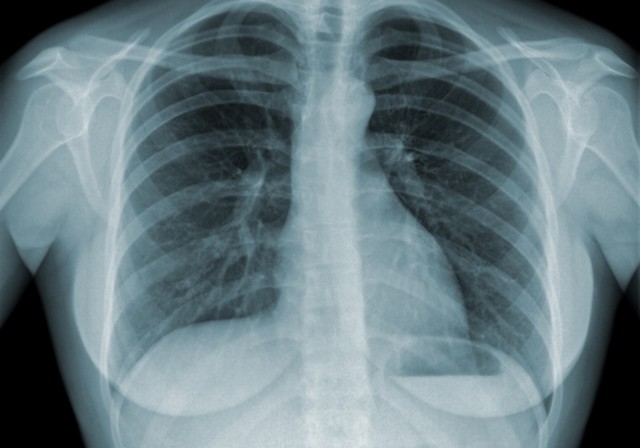

A tuberculose precisa ser tratada de forma rápida, pois os bacilos alojados nos pulmões destroem os outros órgãos. Apenas com uma radiografia o médico pode diagnosticar a doença e indicar o tratamento correto.